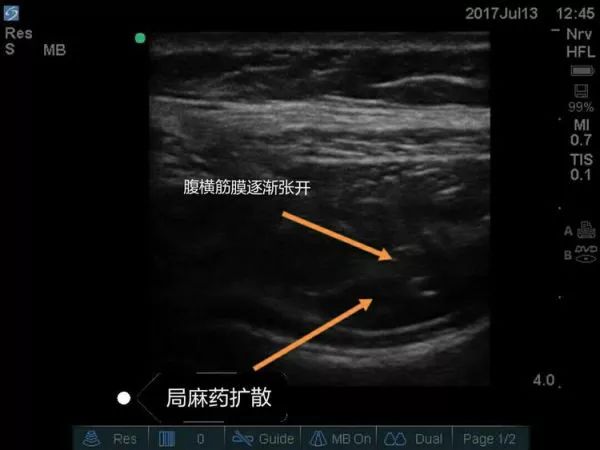

超声引导下腹横平面TAP阻滞要点

③目标: 局麻药在腹横肌和腹内斜肌之间扩散。

④局麻药: 每侧0.25%罗哌卡因20-30ml。

超声下孕妇的腹横筋膜图像

超声引导下腹横筋膜阻滞技术优点:

①为普外科手术如疝气提供麻醉。

②为伴有脊柱病变的剖宫产患者提供麻醉。

③妇科手术的术后镇痛。